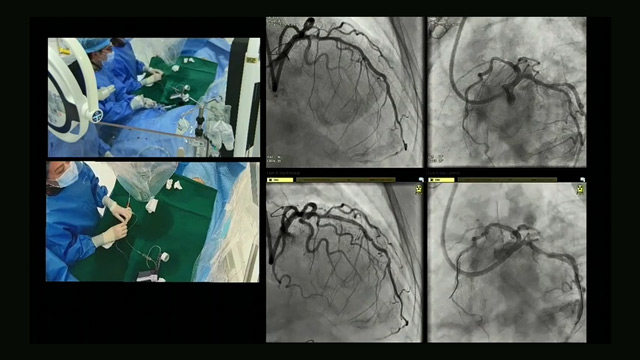

Precision in plaque management: hybrid techniques and IVUS imaging for optimal outcomes

This session offers an in-depth exploration of precision plaque management strategies through hybrid lesion preparation techniques and advanced intravascular ultrasound (IVUS) imaging. It emphasizes the synergistic use of drug-coated balloons and drug-eluting stents to optimize PCI outcomes. Participants will gain a deeper understanding of how cutting...